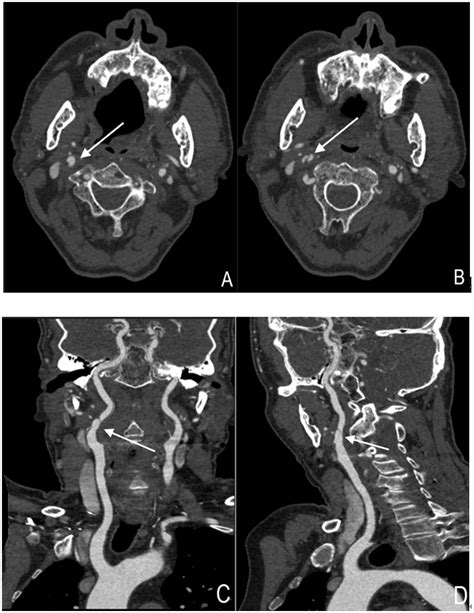

A Carotid Artery Scan can detect a variety of conditions that affect the carotid arteries, including:

• Atherosclerosis: The buildup of plaque in the arteries, which can narrow the blood vessels and restrict blood flow.

• Carotid Artery Stenosis: Narrowing of the carotid arteries, often due to plaque buildup, which can increase the risk of stroke.

• Carotid Artery Dissection: A tear in the artery wall, which can cause blood to leak into the artery and form a clot.

• Carotid Body Tumor: A rare, non-cancerous tumor that develops in the carotid body, a small structure near the carotid arteries.

The results of a Carotid Artery Scan are typically interpreted by a radiologist or vascular specialist. The findings are usually categorized based on the degree of stenosis (narrowing) in the arteries:

Degree of Stenosis Interpretation

0-15% Normal or minimal plaque

16-49% Mild stenosis

50-69% Moderate stenosis

70-99% Severe stenosis

100% Complete occlusion